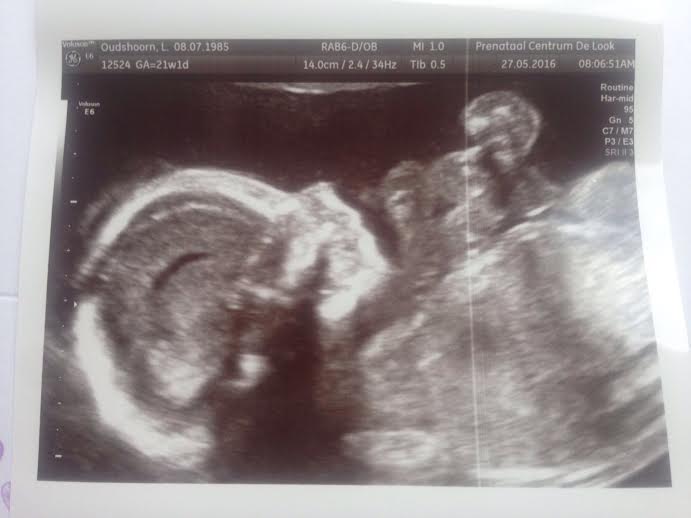

Joehoe, vorige week weer een bijzondere mijlpaal beleefd: de 20 weken echo! Enerzijds omdat het super spannend is of alles goed is met ons kleine ventje en anderzijds betekent het dat de tweede helft is begonnen. Daarnaast is het natuurlijk heerlijk om de baby weer even te kunnen zien, hij was vast alweer hartstikke gegroeid!

Ook al had ik er een heel goed gevoel bij, de kleine trappelt de hele dag door voelbaar in mijn buik en we hebben natuurlijk al een aantal positieve echo’s gehad…als het moment daar is, is het toch weer even super spannend! Ze kunnen zoveel zien en ze controleren ook zoveel. Zullen er wel echt vingers aan de handjes gegroeid zijn, zijn er 2 niertjes aanwezig, is de aanleg van het hartje in orde en hoe zit het met de hartkamertjes? Kortom, een hele check-up voor onze mini baby. Die overigens niet zoveel zin had om mee te werken en zich zover mogelijk verstopte, wat een heleboel geduw op mijn buik opleverde. Uhm, doet u wel een beetje voorzichtig met mijn kind! Voor zover het te zien was, groeit er een gezond kindje in mijn buik en dat maakt mij voor nu de meest dankbare en gelukkigste mama op aarde! Oh ja, en het is nog steeds heel duidelijk een jongetje :-)

De 20 weken echo